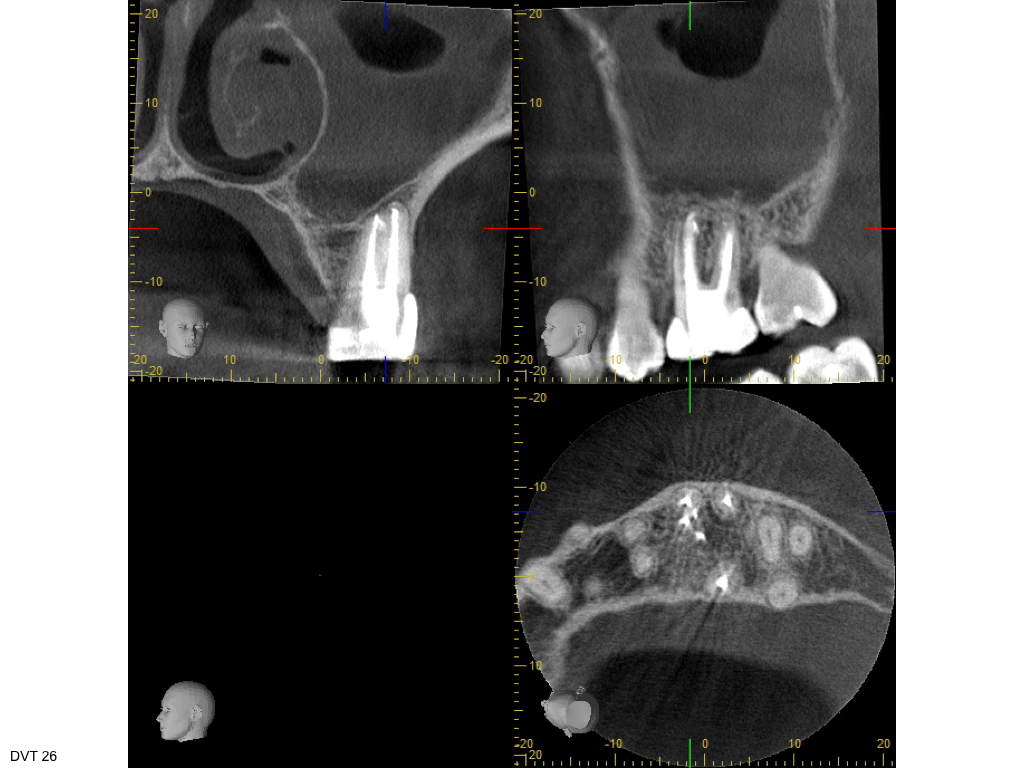

Heilung oder was?